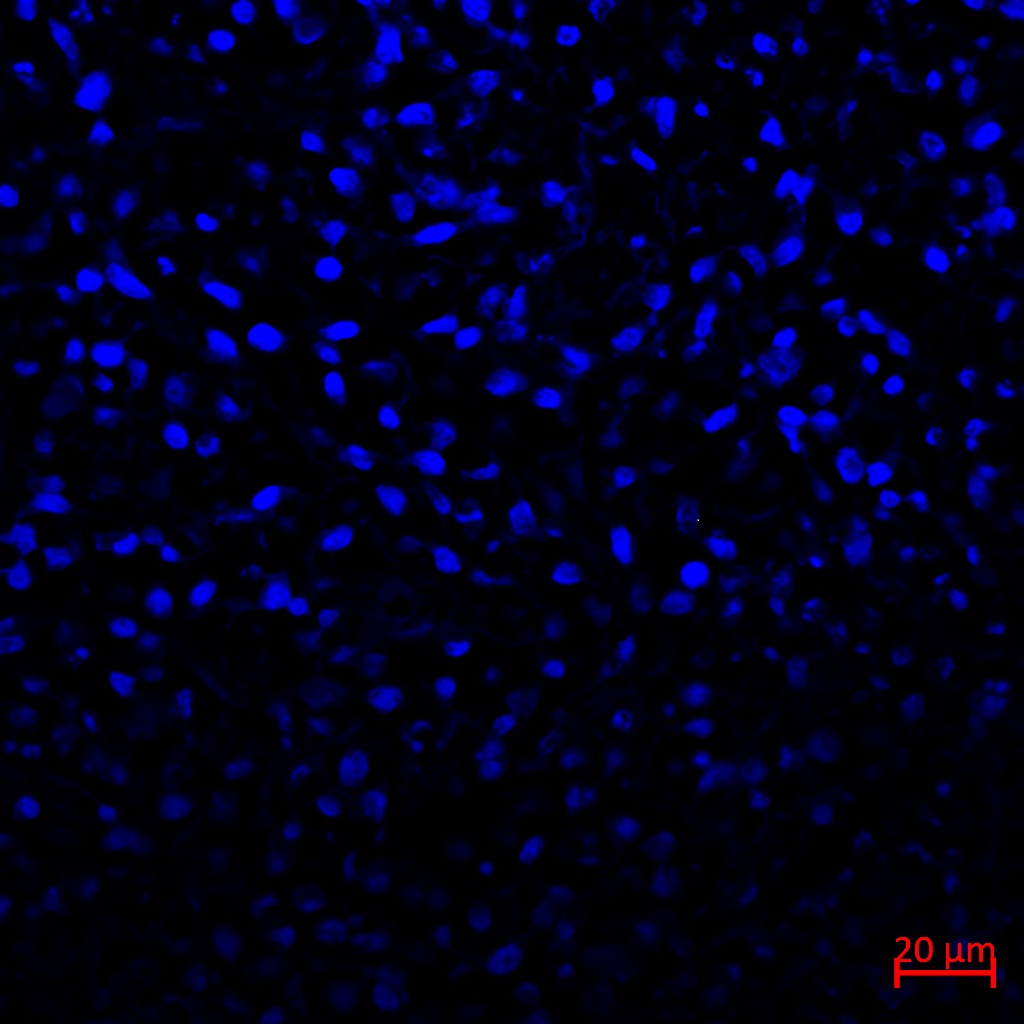

12、TUNEL染色实验结果(小鼠肿瘤荧光法举例)

tunel染色实验结果解读:选择激光共聚焦显微镜观察细胞核经DAPI染色后呈现蓝色,凋亡细胞被FITC标记而呈现绿色。